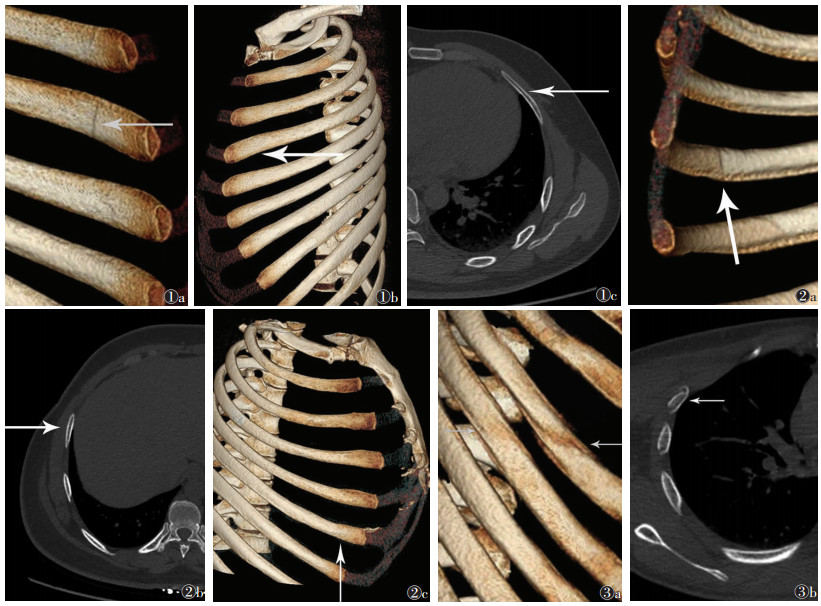

16层螺旋ct多种重建方法在诊断肋软骨骨折中的应用 罕见病 疑难病 会诊平台 专家会诊 网上会诊 医学影像

多层螺旋ct后处理重建在肋骨和肋软骨骨折诊断中的临床应用 中国期刊网

多层螺旋ct后处理技术在肋软骨骨折伤情鉴定中的应用

16层螺旋ct多种重建方法在诊断肋软骨骨折中的应用 罕见病 疑难病 会诊平台 专家会诊 网上会诊 医学影像

16层螺旋ct多种重建方法在诊断肋软骨骨折中的应用 罕见病 疑难病 会诊平台 专家会诊 网上会诊 医学影像